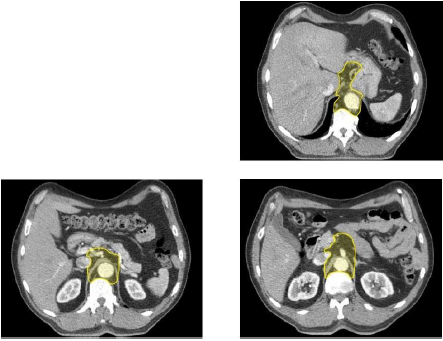

Contouring atlas: the elective lymph nodes

Paraaortic, hepatogastric ligament, celiac lymph nodes.

Below the diaphragm the CTV should be extended inferiorly to the level of the origin of the celiac axis. The CTV will be bounded in the lateral aspect by the vertebral body on the right (usually Th12) and 0.5-1 cm beyond the lateral aspect of the aorta on the left, the vertebral body posteriorly and the pancreatic body anteriorly. Between the level of the gastro- esophageal junction and the celiac lymph

nodes the lesser curvature nodes will be included. In this region the liver will define the right border and the stomach will define the left border. Anteriorly the CTV includes the fatty space between the lesser curvature and the liver.